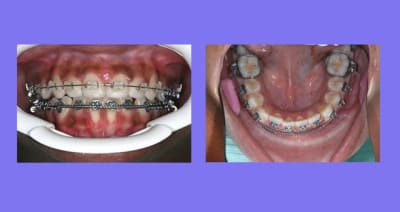

il m'a été reproché de ne pas montrer le cas en entier et de ne pas expliquer comment j’avais traité

Voici le cas depuis le début, traité avec mes Bk. modifiés qui permettent de travailler en passif en début de traitement, en inter-actif au milieu de traitement, avec ou sans les ressorts de Root, et parfois en friction forte en fin de traitement pour les finitions

C’est un cas ancien ou je ne faisais pas assez de photos et ou j’essayais différentes marques de Bk.

soyez indulgent

Reprise du cas au départ

1°) Q.H. Sup pendant 6 mois, désolé, pas de photos

2°) Appareillage MB. Sup et 2 mois après Inf., avec mes Bk. modifiés en position Damon

On peut observer un décalage des points inter-incisifs et des rotations des Inc. Inf.

Voir Photo